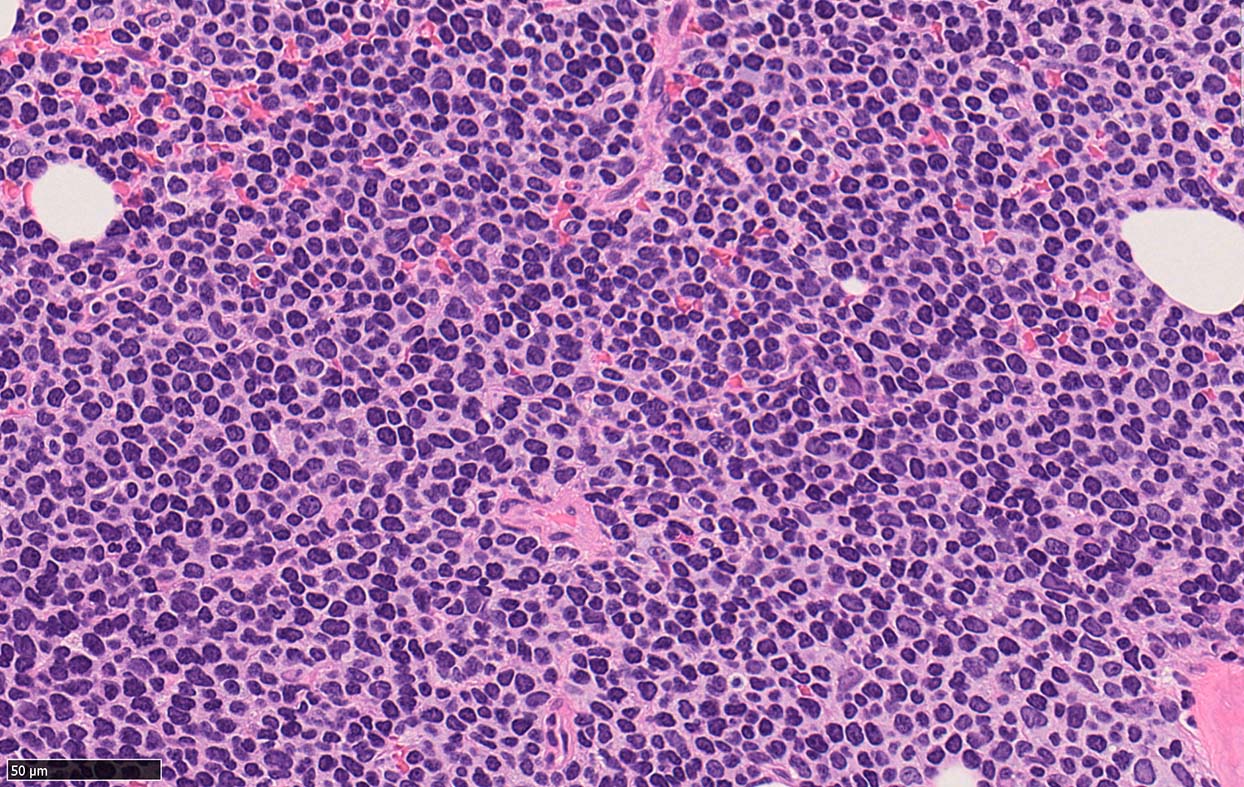

Bone marrow involvement of mantle cell lymphomaの症例

骨髄骨梁間に密なASD-Giemsa陰性の小型~中型円形細胞の浸潤が認められる.

骨髄浸潤細胞所見